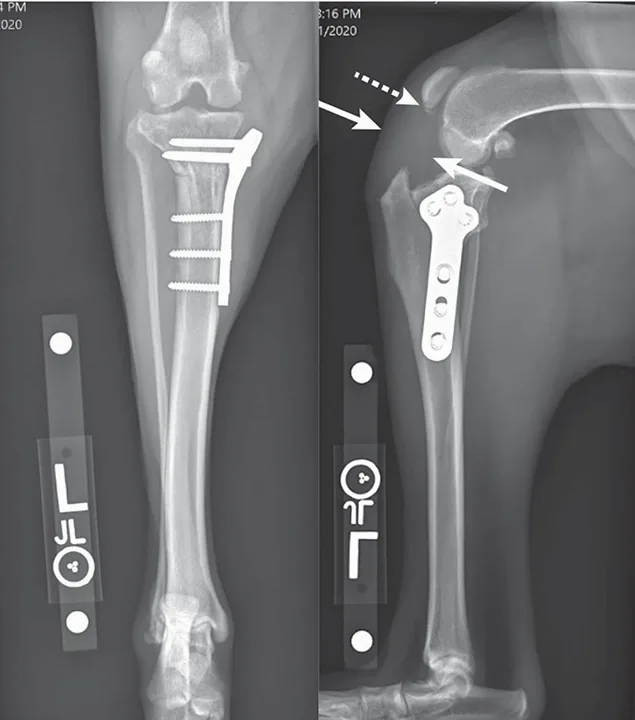

Radiographs from an 8-year-old spayed Rottweiler that underwent TPLO and was diagnosed with a superficial SSI 2 weeks postoperatively at another hospital. The SSI was treated with a 10-day course of antibiotics. The dog was presented to The Ohio State University Veterinary Hospital 6 weeks after surgery for recurrent lameness; the incision was healed, but osteomyelitis was confirmed on radiographs and fine-needle aspirate and cytology. Culture-based antibiotics were prescribed, but the infection did not resolve, the lameness was persistent, and the osteotomy became a nonunion. The patient was euthanized after developing a T3-L3 myelopathy suspected to be related to systemic infection.